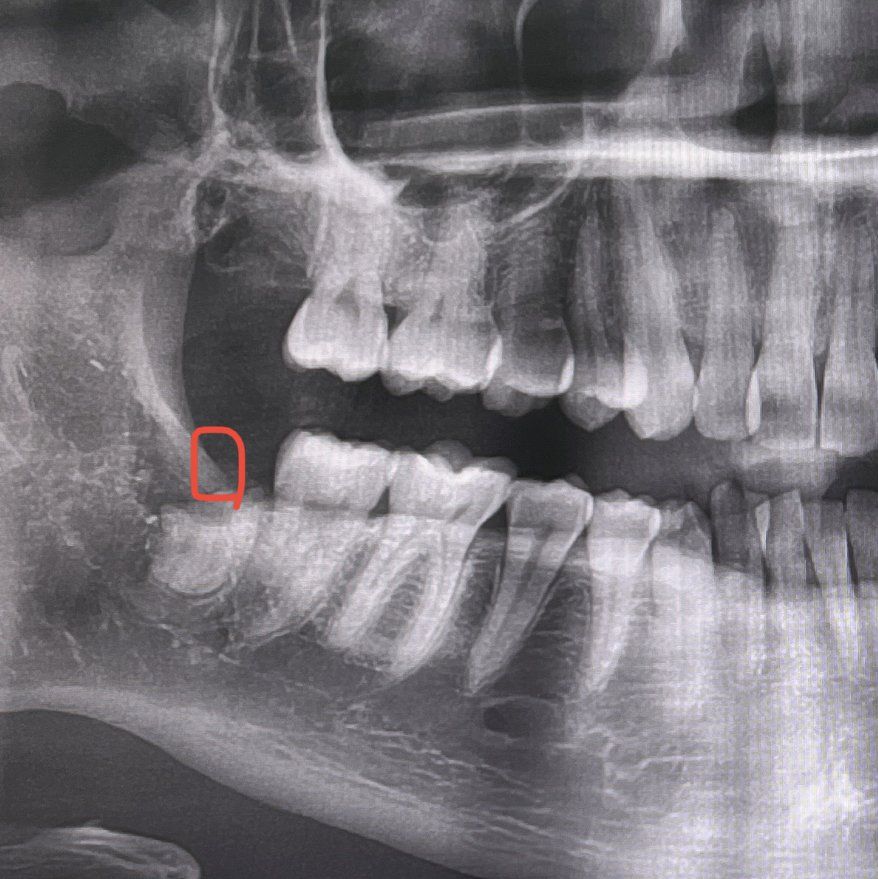

사랑니 발치후 뿌리 발치를 실패했는데요. 사랑니 전문병원에 가면 발치가 가능할까요? (사진첨부)

동네 치과에서 사랑니를 발치하다가 그 치과의사가 발치를 실패해서 뿌리만 남긴 채로 발치를 끝냈는데요.

그리고 사랑니 발치후 동그라미 친 부분에 혀를 대보면 뼈 같은게 닿아서 따가운?느낌이 드는데 시간이 지나면 살이 차거나해서 해결되는건가요? 거울을 보니 아주 작게 하얀게 보이는 것 같아서요.

• 1번 째 사진

뿌리가 많이 남은것으로 보입니다.

이 경우 가능하면 뿌리를 발치하는게 좋아보입니다.

타 병원에서 상담후, 발치는 가능할 것으로 보입니다.

현재 하얗고 딱딱한게 있다면 뼈나 치아조각일 가능성이 있습니다. 우선 타 치과에서 체크를 받아보시기 바랍니다. 감사합니다.